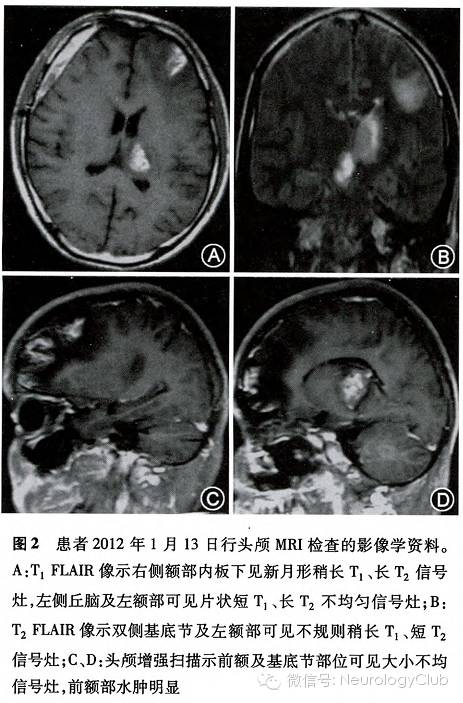

患者男性,24岁,因“急起言语不清,右侧肢体乏力5d”于2012年1月13日收入我院神经外科,于2012年2月4日转入我科。患者入院前5d在外打牌时突发言语不清,右侧肢体乏力,余无不适,未处理;3d后自觉上述症状加重,遂于当地医院查白细胞计数为11×10^9/L,中性粒细胞百分比80.8%,头颅MRI示“双侧基底节及双侧大脑半球内层区多发占位性病变,考虑转移瘤合并出血可能性大”(图1),后转入我院神经外科复查头颅MRI,示“双侧基底节及双侧大脑半球内层区多发占位性病变,病灶内合并出血”(图2),择期在全麻下行右额叶病变切除术,术后症状未见缓解,转入我科。患者发病以来无发热、头痛及意识不清等症状。既往病史(-)。入院体检:头颅右侧颞区可见3cm弧形手术伤口,言语欠清,理解力、定向力、记忆力及计算力均减退,颈稍抗,颏胸3横指,伸舌偏左,右侧肢体肌力Ⅲ级,肌张力增高,右侧膝腱反射及跟腱反射亢进,双侧踝阵挛(+),右侧巴宾斯基征及查多克征(+),余检查无异常。入院查白细胞计数为14.1×10^12/L,脑脊液压力80mmH2O(1mmH20=0.0098 kPa),脑脊液常规+生化检查+病毒全套检查[巨细胞病毒抗体(IgM、IgG)、单纯疱疹病毒I型抗体(IgM、IgG)、风疹病毒抗体(IgM、IgG)、弓形虫抗体(IgM、IgG)、柯萨奇病毒抗体(IgM、IgG)、EB病毒抗体(IgM、IgG)]无异常,病灶区病理学检查示:镜下见蛛网膜较多淋巴细胞、浆细胞浸润,部分脑组织有软化、坏死及脱髓鞘改变,其中见充血、炎性细胞浸润及星形细胞反应性增生,可见散在神经细胞(体积变小,未见卫星现象),未见肿瘤和其他特异性改变。免疫组织化学检查示:髓磷脂碱性蛋白部分(-),而该区神经纤维细丝蛋白及突触素(+),胶质纤维酸性蛋白部锁+),巢蛋白(-),神经元特异核蛋白散在少数(+),Ki-67增生的星形细胞(+),CD45RO及CD3(+),CD20灶状,CD138散在(+)。病理诊断:符合脱髓鞘性脑病(图3)。综合上述检查结果,临床诊断为AHLE。予大剂量甲泼尼龙+阿昔洛韦治疗,病情未见好转,患者家属要求出院。随访2个月后患者死亡。

AHLE又称急性出血性坏死性脑炎,发病机制目前尚不明确,相关研究认为与炎症有关,在患者血清和脑脊液中均可检出炎性因子;还有学者认为与病毒感染有关,包括A型流感病毒和肠道病毒等。AHLE多见于青壮年,以20-50岁多见,多数患者发病前有上呼吸道感染等前驱症状,少数患者发病前有水痘、单纯疱疹等感染,前驱病症持续1-15d后出现神经系统症状,表现为突发高热、头痛、呕吐,甚至肢体麻木、瘫痪,很快意识恶化,进入昏迷状态。体检有脑膜刺激征,眼底多数正常。脑神经损害少见,四肢腱反射低下或消失,可有病理征。外周血象可见以中性粒细胞增高为主的白细胞增高,脑脊液检查细胞数无异常,蛋白可轻度增高。影像学检查MRI优于CT,以T2像和FLAIR像更为敏感,T2像可见双侧多灶性白质高信号,有研究显示病灶为广泛的高信号白质水肿夹杂多发的斑点状低信号出血,但血肿罕见。部分患者基底节、丘脑、脑干、小脑及脊髓也可见异常信号。尽管如此,本病确诊需病理活体组织检查(简称活检)。其病理特点为:①出血性坏死:白质灶内有大小不等的多灶性出血及多灶性小灶状坏死,常为球状或环状坏死,球状灶中间为小毛细血管,周围为外渗的红细胞,环状灶则中央为小静脉,在血管壁或周围可有纤维素渗出或坏死;②静脉周围可有小胶质细胞灶,表现为静脉周围的小胶质细胞增生及脱髓鞘改变;③血管周围血源性浸润:主要在毛细血管及微小动脉周围存在大量的白细胞浸润,以淋巴细胞浸润为主,形成袖套;④部分患者脑组织静脉和小静脉周围存在大量轴突损伤,特别是致死性AHLE多见。有学者认为,弥散性坏死灶、血管周围出血是AHLE的典型病理特征。AHLE目前尚无特效治疗,传统治疗包括大剂量皮质类固醇冲击、静脉注射免疫球蛋白以及血浆置换。有报道IL-1拮抗剂阿纳金岭可显著改善AHLE患者的病情。本例患者起病急骤,神经系统症状出现较早,根据临床表现易误诊为脑血管病,影像学检查无特异性,但多发占位并出血,最初诊断为瘤卒中,行外科手术疗效欠佳,最后依靠病理学检查确诊为AHLE。因此,遇到此类患者应尽早行病理活检确诊,并提高对病变的认识,尽快开展相关治疗,提高患者的生存率。